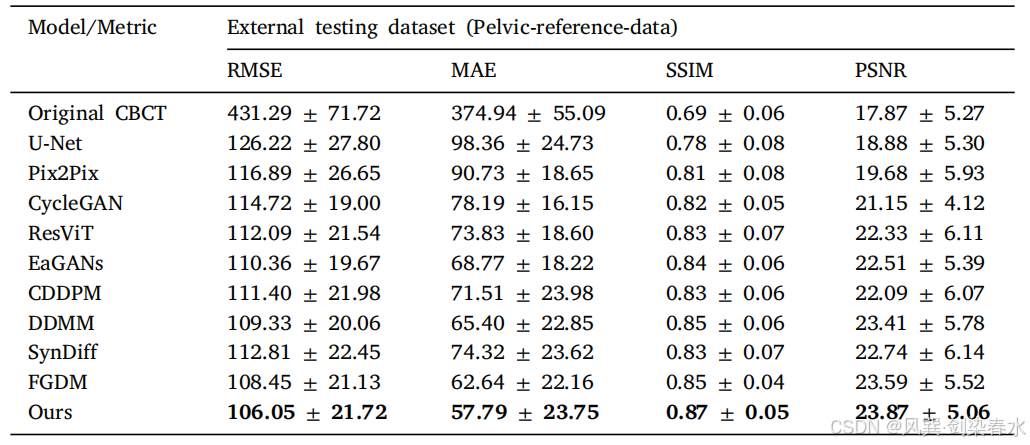

Table 2 | 外部骨盆测试数据集的实验结果:

Figure 4 | 外部骨盆测试数据集可视化:(A1-J1)和(A2-J2)是 CT 与相应预测的 sCT 之间的绝对差异图像,CBCT 的显示窗口在外部测试数据集中为 [−750,250] HU,而 CT 和 sCT 的显示窗口则为 [−160,240] HU;